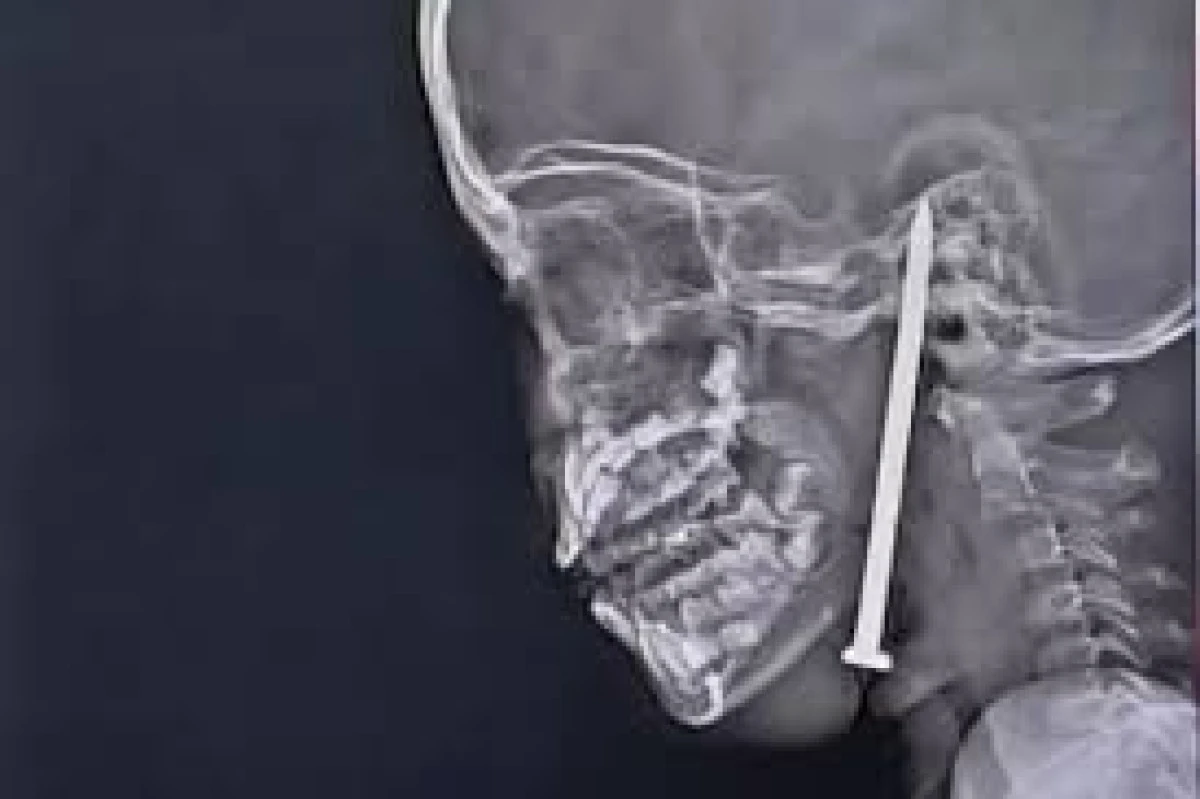

Hindistan'da 7 yaşındaki bir kız çocuğunun beynine saplanan 8 santimetrelik çivi, doktorlar tarafından başarıyla çıkarıldı. Oyun oynarken düşen küçük kızın boynunu ve çenesini delen çivi, beynine kadar ulaştı. Tomografi, çivinin hayati damarların çok yakınından geçtiğini gösterdi.

Hindistan'da gerçekleşen olağanüstü bir ameliyatla, doktorlar 7 yaşındaki bir kızın beynine saplanan 8 santimetrelik çiviyi başarıyla çıkardı.Küçük kız oyun oynarken düştü ve yerdeki ince bir inşaat çivisi, boynunu ve çenesini delerek beynine kadar ulaştı. Korkunç olay, 15 Mayıs'ta Uttar Pradesh eyaletinin Nawajpur köyünde meydana geldi.

Yapılan tomografi, çivinin alt çeneden girip kafatasına kadar ilerlediğini ve hayati damarların çok yakınından geçtiğini gösterdi. Ameliyat, ertesi gün (16 Mayıs'ta) Dr. Vaibhav Jaiswal ve Dr. Sameer Mishra tarafından Lucknow'daki King George Tıp Üniversitesi Travma Merkezi'nde yapıldı.Şişlik, enfeksiyon ve beyinle ilgili riskler nedeniyle küçük kız solunum cihazına bağlandı ve yoğun bakımda 10 gün boyunca yakından takip edildi.29 Mayıs'ta normal servise alındığında tamamen bilinçliydi, tepkileri yerindeydi ve ciddi bir nörolojik hasar izine rastlanmadı. Doktorlar, kızın tamamen normal bir hayat sürdürebileceğini söylüyor.